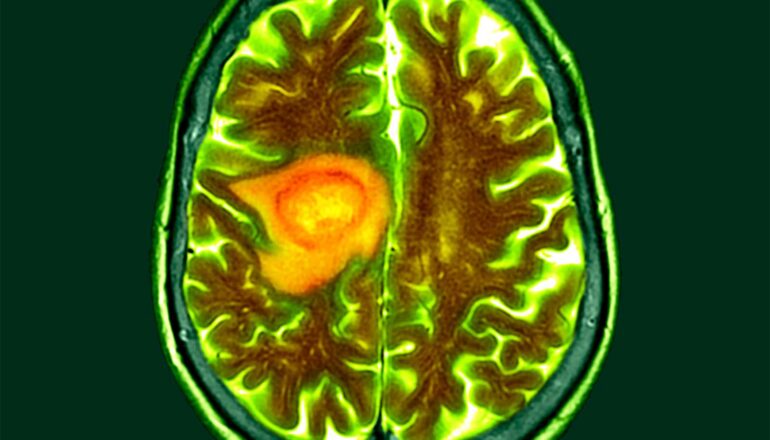

A brain scan shows a brain tumor highlighted in orange and yellow.